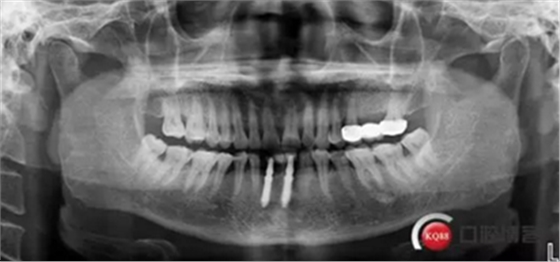

下圖是術(shù)后照片 治療過程 術(shù)前測(cè)量上下牙長(zhǎng)度比例,確定水激光冠延長(zhǎng)深度約3mm,拔除31、41,在術(shù)區(qū)減低牙槽嵴高度,32、42位點(diǎn)種植MINI型一段式種植體,使用臨時(shí)愈合帽行暫時(shí)性修復(fù)。

治療前后照片顯示患者上下臨床牙冠比例協(xié)調(diào),患者對(duì)臨時(shí)修復(fù)體效果十分滿意。當(dāng)然有待后期愈合及長(zhǎng)期的臨床隨訪,以觀察遠(yuǎn)期臨床效果。將水激光應(yīng)用臨床冠延長(zhǎng),有利于精準(zhǔn)去除骨量,利于術(shù)后愈合。而MINI型一段式種植體滿足骨寬度不足,及臨時(shí)修復(fù)打下堅(jiān)實(shí)基礎(chǔ)。